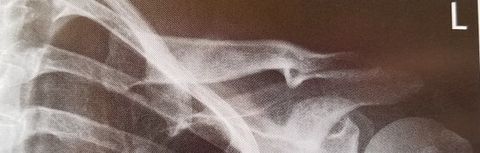

| AP Clavicle | MCP is tilted anteriorly |

| AP Clavicle | MCP is tilted posteriorly |

| AP Clavicle | Patient is rotated towards affected shoulder |

| AP Clavicle | Patient is rotated towards unaffected shoulder |

| AP Clavicle | ANATOMY: entire clavicle with both AC and SC joints included CRITERIA: entire clavicle and acromion are included lateral clavicle bows up, while the medial clavicle is superimposed by ribs 2-3 POSITIONING: CR perpendicular @ midclavicle |

| AP Axial Clavicle | ANATOMY: entire clavicle and both joints included CRITERIA: clavicle is more horizontal, and projected above the scapula and ribs medial end may be superimposed by ribs POSITIONING: CR angled 15-30 degrees cephalic @ midclavicle |